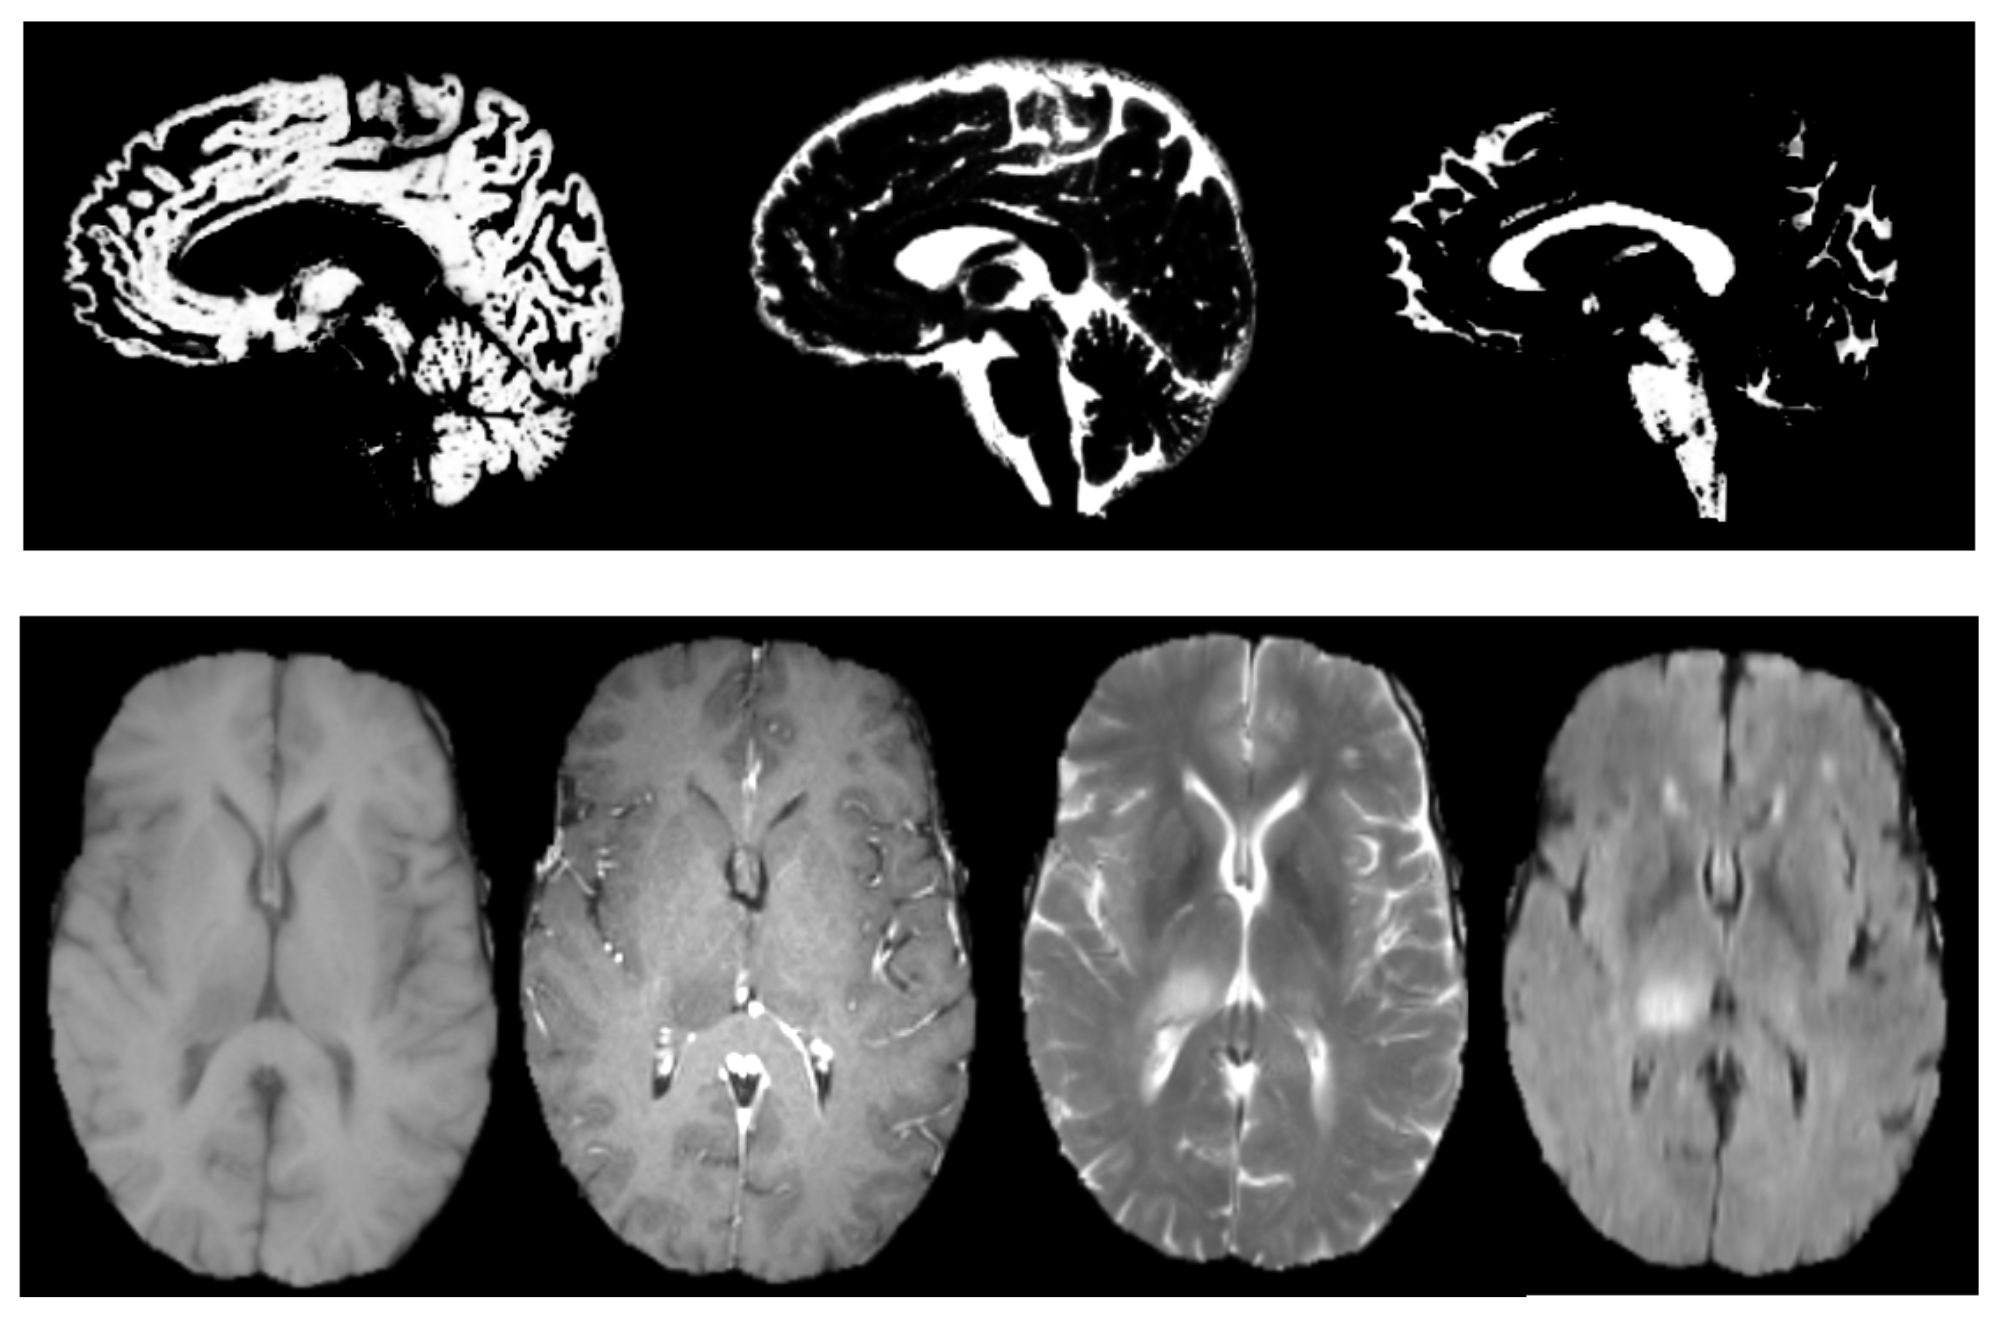

4.1. Attention Deficit Hyperactivity Disorder Diagnosis

4.2. The Brain Tumour Segmentation on BRATS 2017